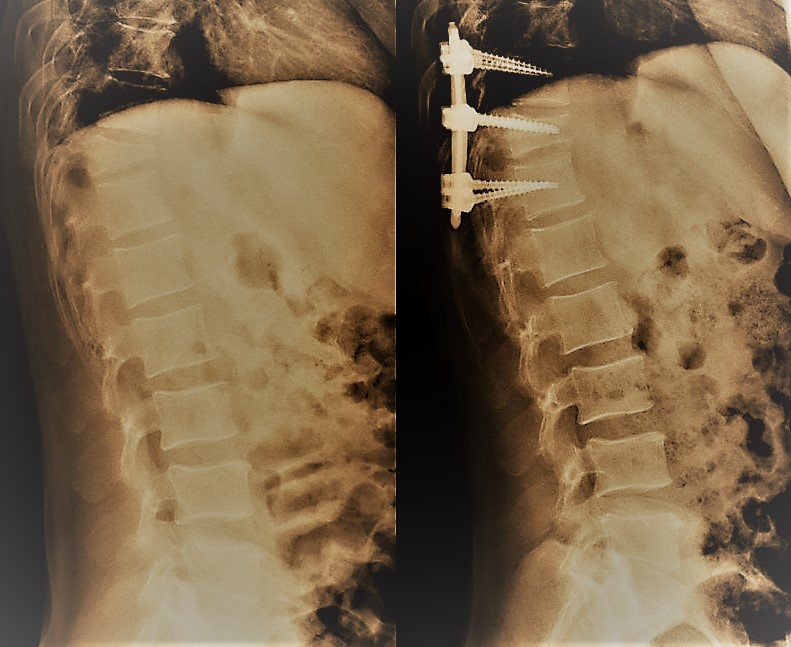

- Accesos mínimamente invasivos a columna como medio para la preservación de la musculatura paraespinal

- La Microcirugía como herramienta transversal en Cirugía de Columna y Neurocirugía Oncológica

- Medicina de precisión aplicada a la Cirugía de Columna